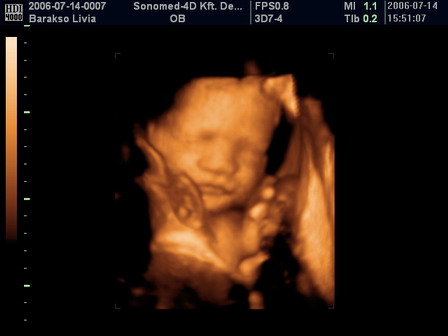

Azért tegnap elmentem a 4D UH-ra, bár a sok köhögéstől, sokszor elmosódott a kép. Na meg Peti is beintett és mindig elfordult. De azért elkaptunk egy egy pillanatot. Sokat csücsörített a szájával, nyújtogatta a nyelvét, nyitogatta a szemét és tömködte az ökleit a szájába. És egyszer úgy tűnt, mintha vigyorogna. Olyan, mint egy kis kövér Buddha, nagyon édes, majd megpróbálok feltenni képet, csak DVD-ről lementeni nehéz

Ő a drága! :)

Kép